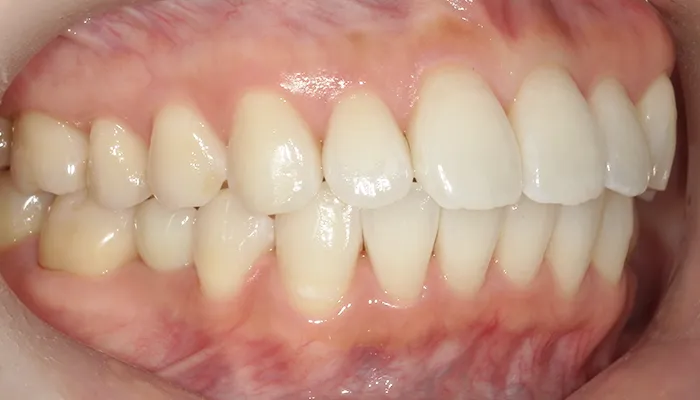

治療前

口腔内写真とレントゲン写真

右下5番は大きく崩壊しており、保存不可能な状態でした。

また、下顎前歯部を中心に叢生があり、歯列が不均一でした。咬合関係が不安定で、清掃性も低下していました。

全体的に歯の色もやや黄みを帯びており、患者様からも審美的な改善希望が強くありました。